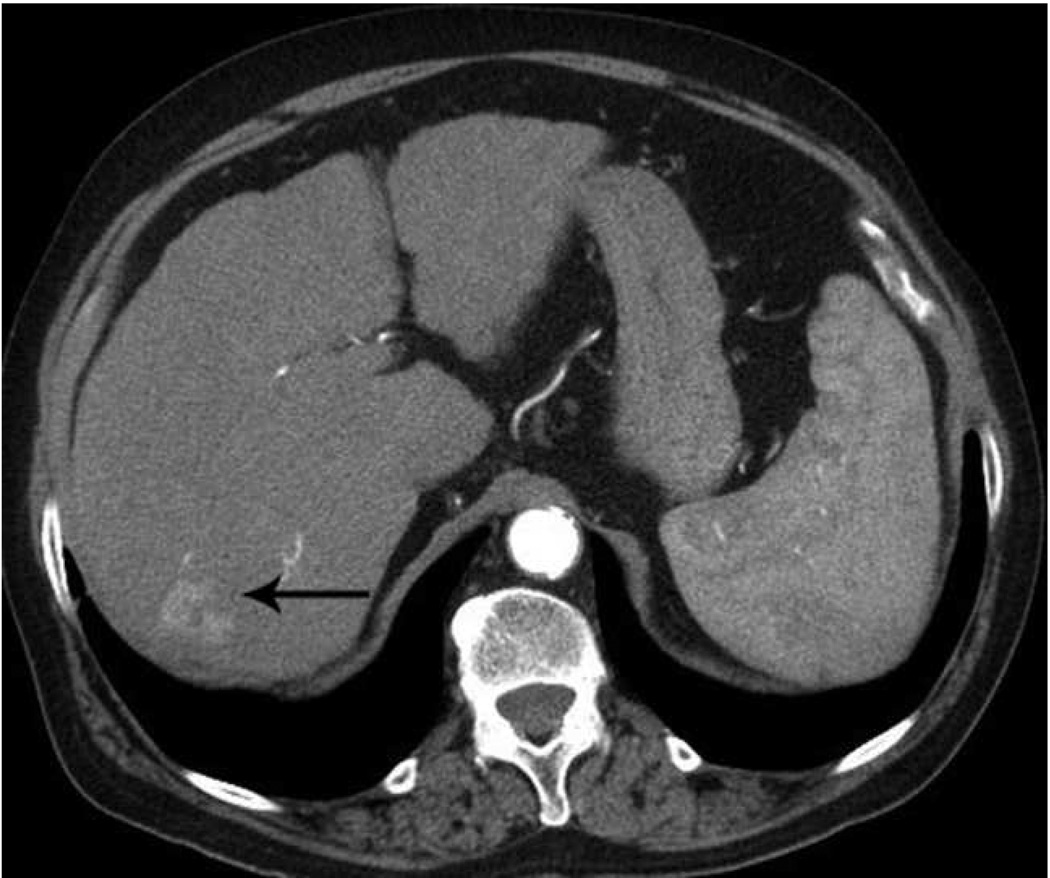

Currently available microwave systems continue to face technical limitations, and this has prevented the potential of microwave from being realized in the clinic to date. Major limitations include underpowered systems, shaft heating, large diameter probes, long and relatively thin ablation zones which have limited clinical application (especially in small bone lesions such as osteoid osteomas and solid organ surface lesions). Similarly, there is still some unpredictability to the size and shape of the zone of ablation which may be related to technical factors (Figures 8, 9)

Figure 8.

Microwave ablation of small hepatocellular carcinoma using the Covidien Evident™ system. Pre ablation CT (a) demonstrates a small hepatocellular carcinoma (arrow) in a patient with hepatitis C and relatively mild cirrhosis. Two probes were placed, and ablation was performed with a large area of gas bubbles forming on the periprocedural US (b). These probes, run at 45 W for 10 minutes, generated a larger than expected ablation zone (large arrow) that extended into the body wall (small white arrow), seen on post procedure CT (c).

Figure 9.

Microwave ablation of liver lesion using Covidien Evident™ system. Pre procedure CT (a) demonstrates a small hepatocellular carcinoma (arrow) in a mildly cirrhotic liver. Two probes (b) were placed into the lesion and run at 45 W for 10 minutes, similar to the case in figure 5. However, a relatively small area of hyperechoic change was identified on the periprocedural US (arrow, b) and the immediate post procedure CT image (arrow, c) demonstrates a much smaller ablation zone with residual tumor seen along the anterior and medial margins at one month follow up (arrow, d). The variation in result between these two cases may be related to increased sensitivity of microwaves to probe placement and phasing.